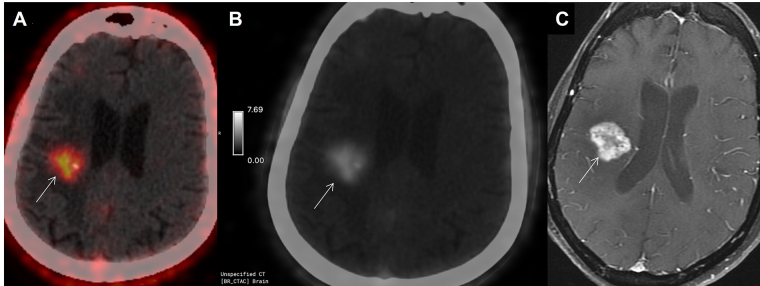

Fibroblast-activated protein (FAP) expression in glial cells is attributed to FAP-positive foci on tumor vessels and neoplastic cells. Preclinical and pilot studies have shown FAP expression in high-grade gliomas. We aimed at comparing PET imaging with FAP-inhibitor (FAPI-PET) with current standard, i.e., fluoro-ethyl tyrosine (FET) PET in post-treatment setting to differentiate recurrence and post-treatment changes. 6 patients with WHO Grade III and IV glioma who received standard treatment underwent Ga-68-FAPI-04 PET/CT (FAPI-PET/CT). Tracer uptake greater than background was considered positive. FET PET was performed and interpreted as per institutional standards, which formed the basis of treatment decision. There was concordance between FAPI expression and FET uptake in 5 patients suggestive of disease recurrence. There was no FAPI expression seen in 1 patient, in whom FET PET was suggestive of post-treatment changes. FAPI PET uptake correlated with amino acid expression to differentiate post treatment changes from recurrence in high-grade glial tumors; further validation with prospective study and histopathological confirmation is needed.

Abstract Image